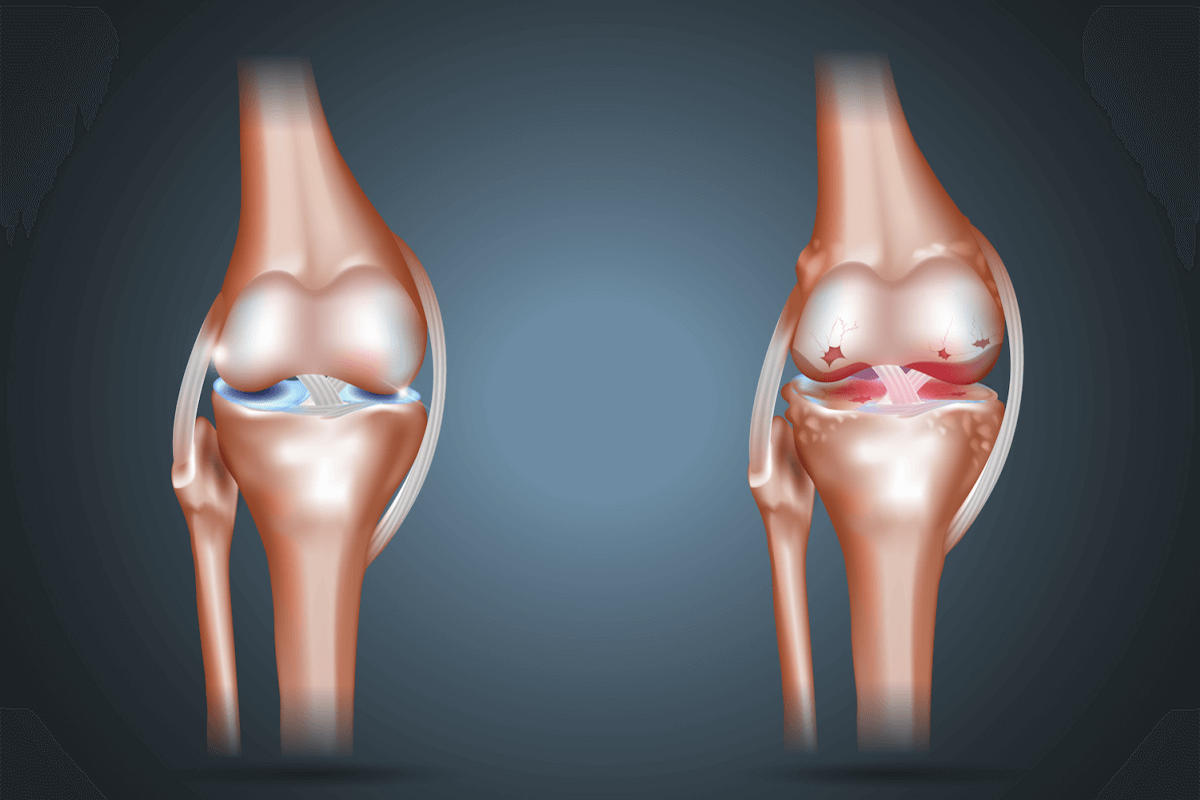

Οι οστεοχόνδρινες βλάβες του γόνατος αποτελούν παθολογικές αλλοιώσεις που αφορούν τον αρθρικό χόνδρο και το υποχόνδριο οστούν. Πρόκειται για κλινική οντότητα ιδιαίτερης σημασίας, καθώς ο αρθρικός χόνδρος δεν διαθέτει αιμάτωση και νεύρωση, γεγονός που περιορίζει σημαντικά τη δυνατότητα αυτόματης επούλωσης και ευνοεί τη χρόνια εξέλιξη της βλάβης.

Οι βλάβες αυτές μπορεί να οδηγήσουν σε επίμονο πόνο, λειτουργικό περιορισμό και, εάν δεν αντιμετωπιστούν έγκαιρα, σε δευτερογενή οστεοαρθρίτιδα.

Ο αρθρικός χόνδρος του γόνατος λειτουργεί ως προστατευτικός ιστός που μειώνει τις τριβές, απορροφά τους κραδασμούς και εξασφαλίζει ομαλή κίνηση της άρθρωσης. Η καταστροφή ή η αλλοίωσή του μπορεί να προκληθεί από οξείες κακώσεις, όπως τραυματισμούς με στροφικό μηχανισμό ή πτώσεις, αλλά και από επαναλαμβανόμενη μικροτραυματική καταπόνηση, ιδιαίτερα σε αθλητές.